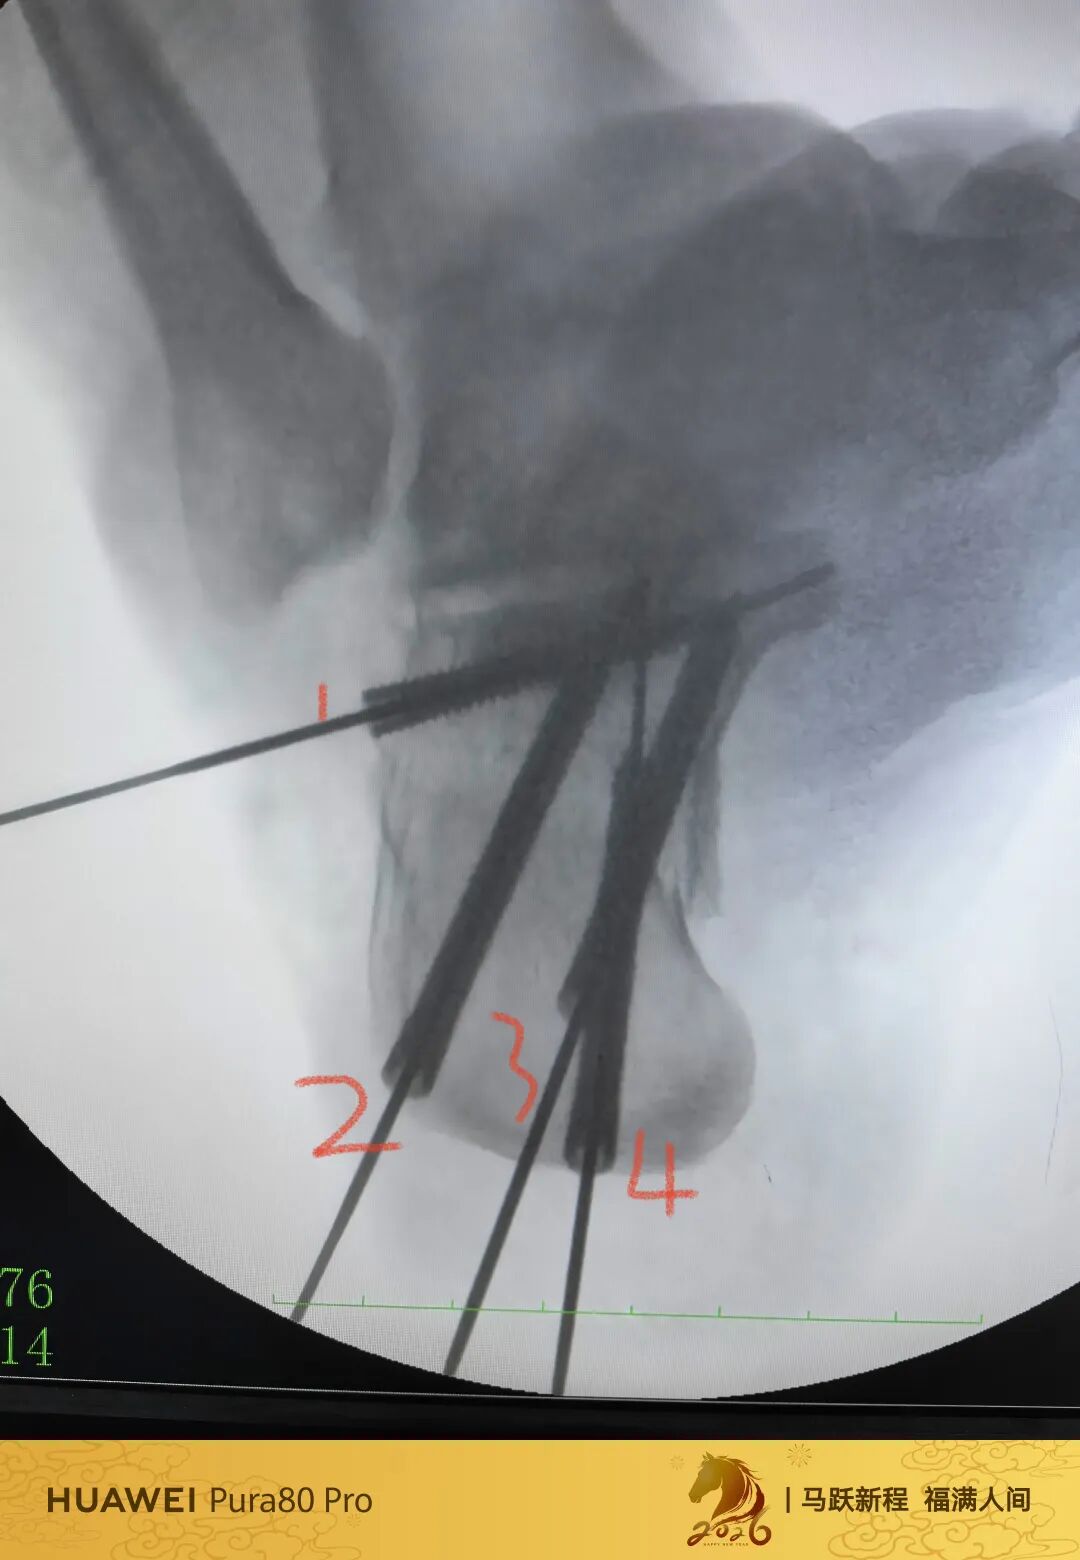

第60例跟骨微创了,虽然已经彻底放手,尽量只动嘴,但还是有小问题小瑕疵,无法完全避免。